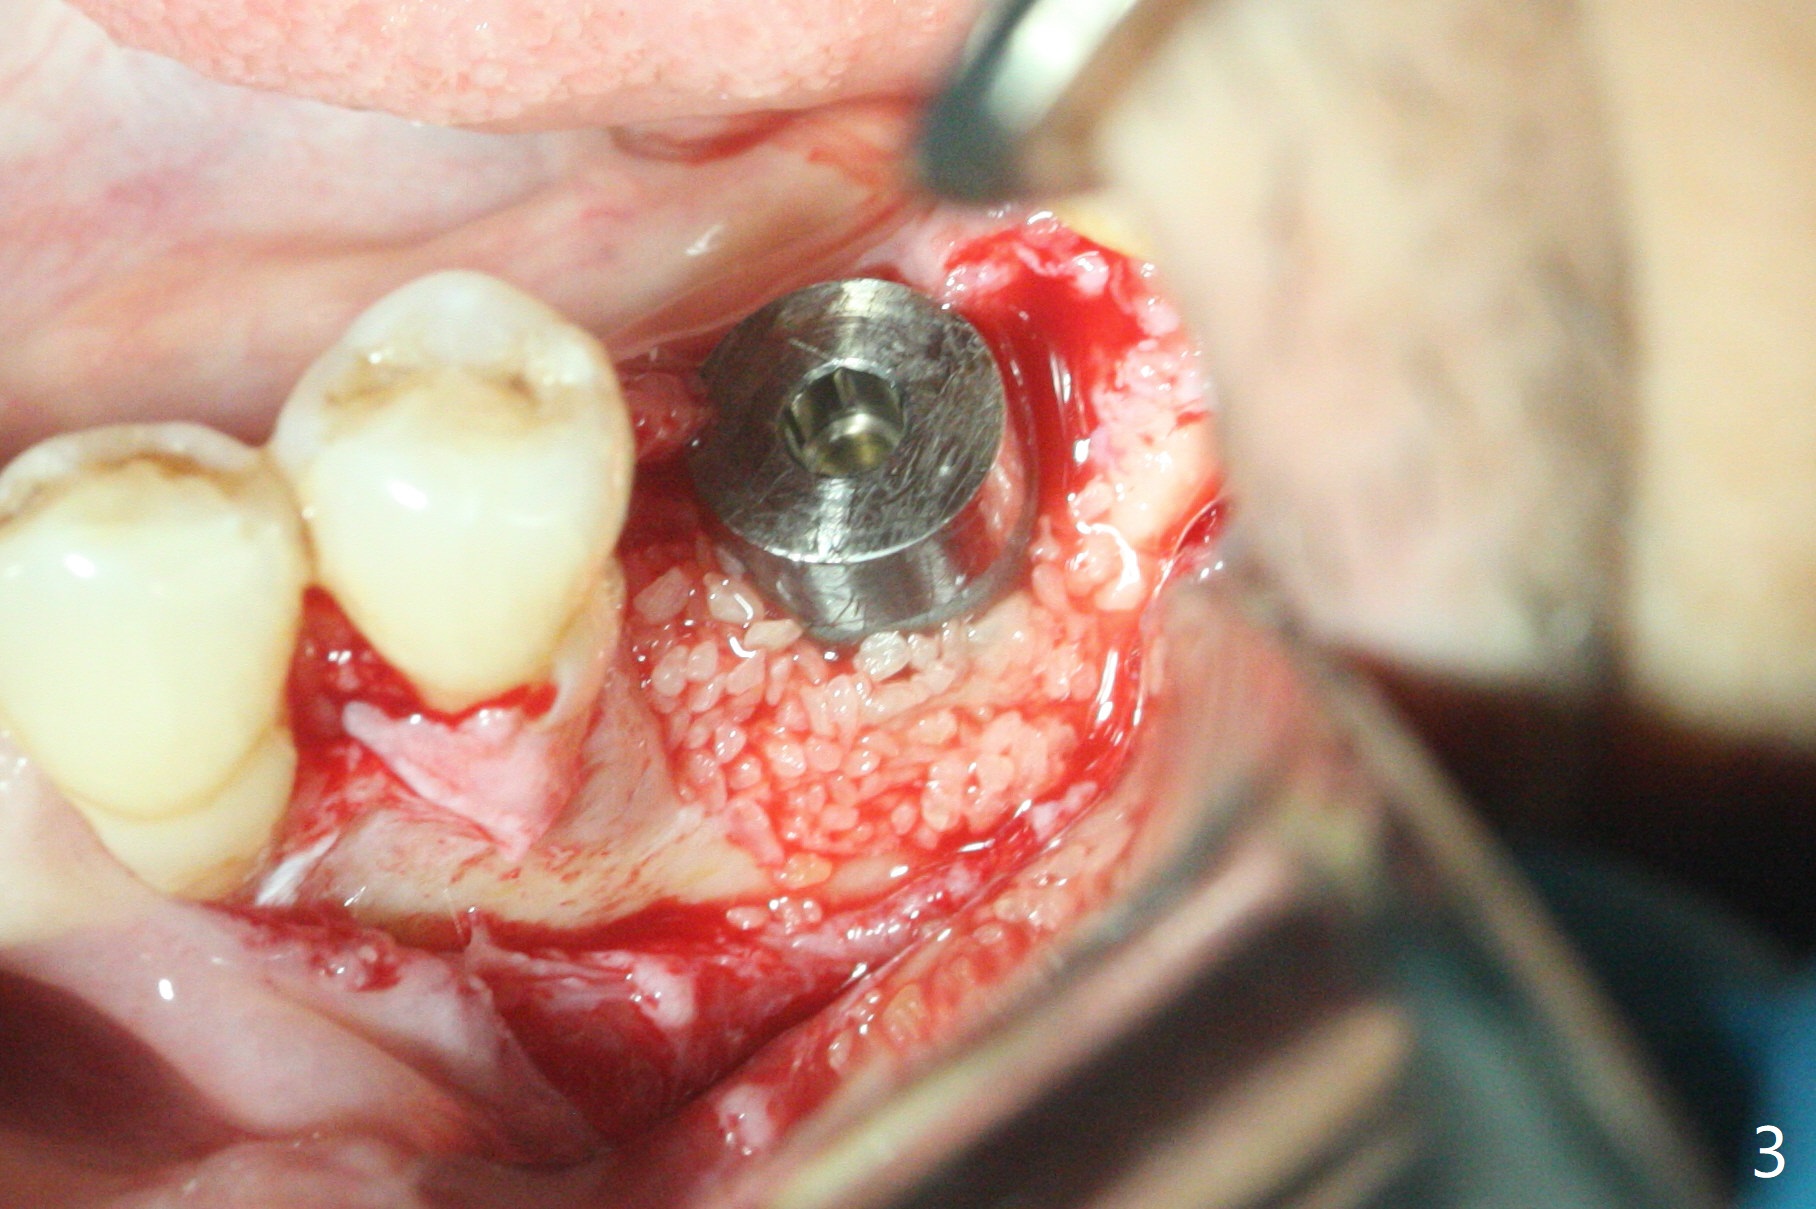

左下6植体周围炎诊断后两周,病人回来做植骨,服用抗菌素一周,炎症有所减轻,但口腔卫生不佳(图一)。软组织水平植体表面菌斑去除后,才切开,清除肉芽组织,钛刷(图二),双氧水擦洗,放置粘性骨粉(图三)和PRF膜,缝合,安置基台(图四:A),有利于牙周敷料固定。术后第二天病人汇报左下唇麻木,不肯用药;第六天回来(图五),麻木造成嘴唇创伤,同意服用Medrol Dosepak。